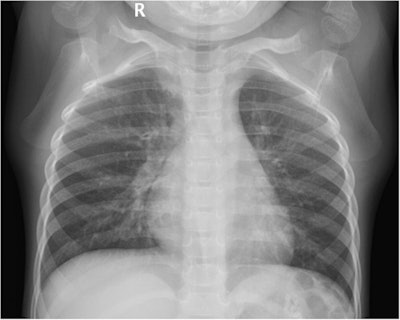

Chinese researchers analyzed radiation doses children received in three different body positions during diagnostic digital x-ray exams: supine anterior-posterior (AP) projection, standing AP projection, and standing posterior-anterior (PA) projection. They found children in the supine anterior-posterior position received higher doses, while those in the standing posterior-anterior position received the lowest dose.

Digital chest x-ray is used to diagnose respiratory illness in children, but studies suggest that because they are more sensitive, radiation-induced cancer may be up to three times higher in children than adults. Standing anterior-posterior and standing posterior-anterior digital chest x-rays are primarily used for cooperative children, while the supine anterior-posterior projection is often selected for uncooperative children because it constrains their motion and results in better image quality, the authors wrote.

The irradiation field was minimized as much as possible and included the apexes of the lungs, clavicles, and the costophrenic angle and the edges of the thoracic walls. The dose area product (DAP) and the entrance surface dose (ESD) were recorded after each exposure.